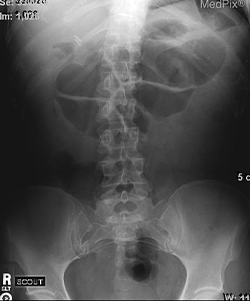

En los exámenes de laboratorio llama la atención la presencia de leucocitosis, elevación de VSG y PCR, así como anemia normocítica hipocrómica. En la radiografía de abdomen encontramos lo siguiente.